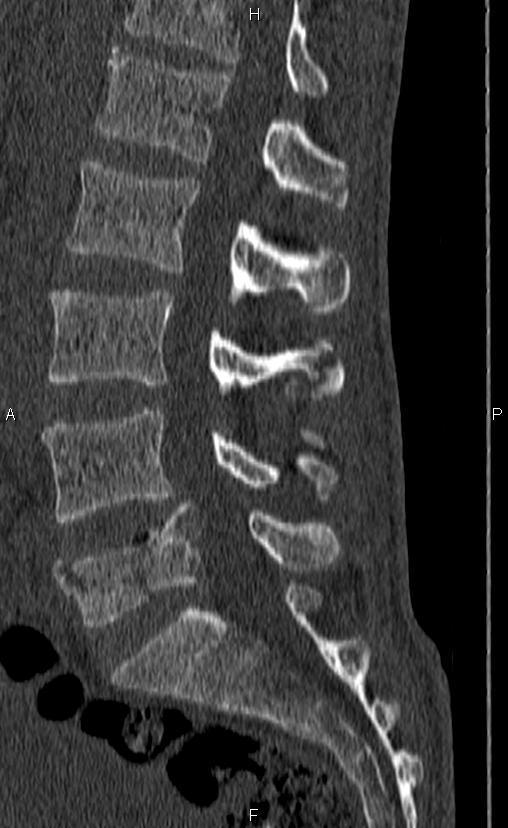

Rachis dorso-lombaire

Mohammad Taghi Niknejad, Radiopaedia.org. From the case rID: 93541

Si présence d’une fracture et ou d’un tassement vertébral à la radio, compléter par une TDM rachidienne puis avis neurochirurgical.